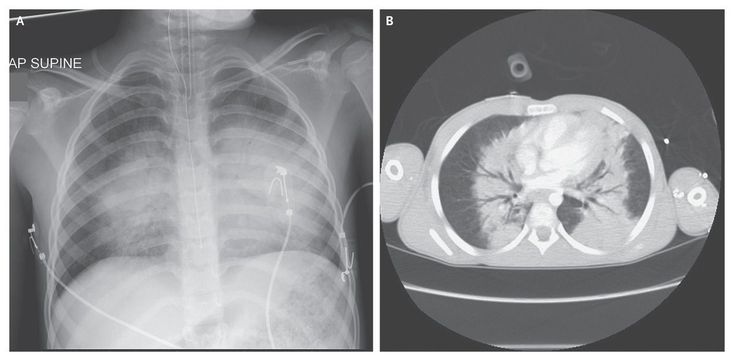

An 8-year-old boy was injured when an improvised explosive device (IED) detonated very close to him. He had multiple wounds to his face, chest, abdomen, legs, and right arm caused by fragments from the IED. He was intubated en route to the hospital owing to airway obstruction and cardiovascular instability. Chest radiography (Panel A) and computed tomography (Panel B) revealed typical appearances of blast lung (pulmonary barotrauma), with interstitial and alveolar filling defects and prominent air bronchograms in a “butterfly” pattern. Lung-protective ventilation was provided with the use of a volume-controlled, pressure-limited mode. The partial pressure of arterial oxygen was normalized with ventilatory support, with a fraction of inspired oxygen of 0.4 to 0.6. Exploratory laparotomy revealed hemoperitoneum and multiple perforations of the small bowel and colon. Two days after the injury, the patient suddenly became hypoxemic and ventilation became extremely difficult. It was discovered that the tube was blocked by a large blood clot caused by pulmonary hemorrhage due to the blast lung. The endotracheal tube was replaced. The patient was successfully extubated after 1 week. On day 19, he was discharged home for palliative care after intestinal failure that was due to multiple small-bowel anastomotic breakdowns attributed to polytrauma and preexisting malnutrition. No further information was available after discharge.